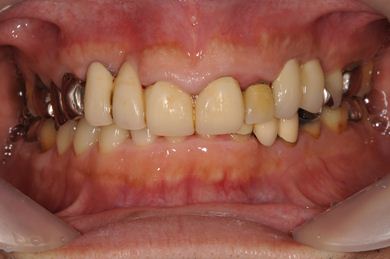

インプラントの症例写真 IMPLANT

抜歯即日スピードインプラント治療

| 治療内容 | インプラント2本(抜歯即日スピードインプラント)、ハイブリッドセラミック2本 | ||||||||||||||||||||||||||||||||